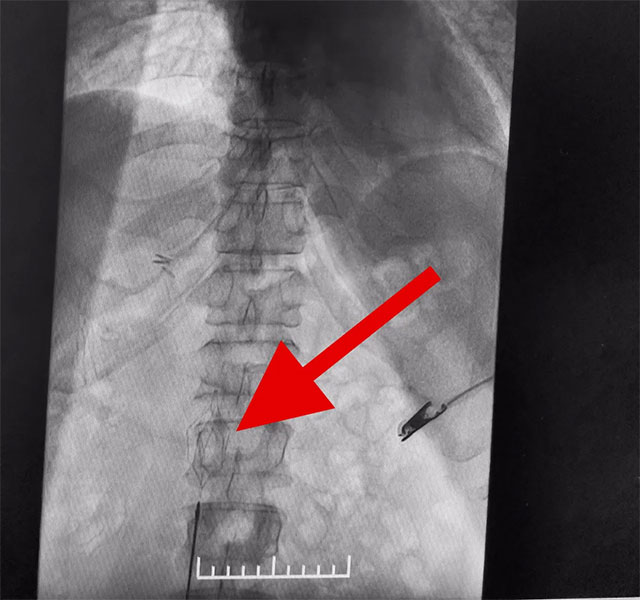

在征得家屬同意后,6月12日,張琪博士團隊為患者進行了下腔靜脈濾器置入手術。張琪博士在醫(yī)護團隊協(xié)助下將一個形似傘狀的人工濾器經患者右側股靜脈穿刺迅速置入下腔靜脈,“網”住了通往心血管和肺部的致命栓子,阻擋血液栓子進入肺動脈,及時挽救了患者生命。

▲ 下腔靜脈濾器置入成功

下腔靜脈濾器置入是為了預防下腔靜脈系統(tǒng)栓子脫落引起肺栓塞而設計的一種裝置,分為永久性和可回收兩種。可回收濾器可經健側股靜脈、亦可經頸內靜脈置入。該手術通過濾器輸送器,將濾器在X線透視下送入,確定位置無誤后,后撤輸送器直至濾器彈開、釋放。